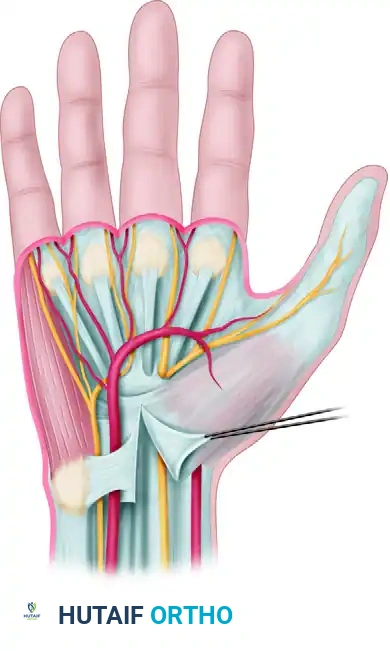

Anatomical relationships of the deep transverse carpal ligament, highlighting the proximity of the median nerve, ulnar nerve, and superficial palmar arterial arch.

The median nerve traverses the carpal tunnel alongside nine flexor tendons (four flexor digitorum superficialis, four flexor digitorum profundus, and the flexor pollicis longus). Two critical branches of the median nerve demand meticulous attention during surgery:

The Superficial Palmar Arterial Arch